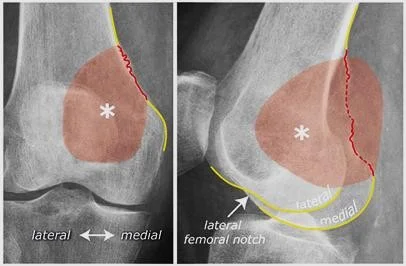

Mechanism â Jumped from the 2nd floor

Presentation â Pain and swelling around the right knee

Site â Lateral tibial plateau

Type â Simple

Fracture line â Vertical split

Intraâarticular â Yes

Displacements â Small gap in the articular surface

Special issues â Requires surgery for absolute stability

A 32âyearâold patient fell from a palm tree and now presents with pain and swelling around the left knee.

- Site: Lateral tibial plateau

- Fracture type: Comminuted

- Fracture line: Vertical split

- Displacement: Depressed

- Special issues: CT scan required for detailed assessment

- Management needed: Surgical intervention